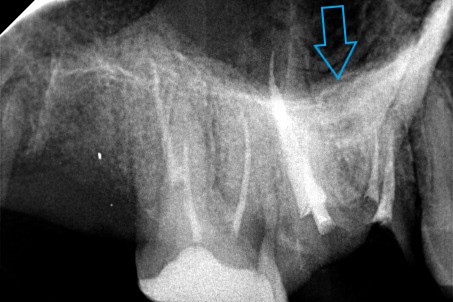

Η ασθενής επιθυμούσε να αντικαταστήσει 2 παλιά σφραγίσματα αμαλγάματος. Αποφασίστηκε η κατασκευή δύο ολοκεραμικών θηκών. Σύμφωνα με το γερμανικό πρωτόκολλο για τις απονευρώσεις δοντιών, πριν από μία προσθετική δουλειά θα πρέπει να ελέγχονται παλιές απονευρώσεις που υπάρχουν ήδη σε ένα δόντι. Σε περίπτωση που αυτές είναι αμφιλεγόμενες, τότε ενδείκνυται η επανάληψη απονεύρωσης, ώστε να μην προκύψουν στο μέλλον προβλήματα με το δόντι ενώ θα έχει κολληθεί η προσθετική δουλειά.

Στο συγκεκριμένο περιστατικό πραγματοποιήθηκε επανάληψη απονεύρωσης στο πρώτο δεξιό γομφίο. Στη διάρκεια της διαδικασίας εντοπίστηκε και τέταρτος ριζικός σωλήνας, ο οποίος δεν είχε βρεθεί στην πρώτη παλιά απονεύρωση. Η εγγύς ρίζα είχε ενασβεστιωθεί με τα χρόνια και δεν ήταν δυνατόν να επεξεργαστεί ο ριζικός σωλήνας σε όλο το μήκος του. Όμως όλες οι ρίζες παρασκευάστηκαν και καθαρίστηκαν πολύ καλά και στη συνέχεια εμφράχθηκαν ερμητικά.

ΠΡΙΝ

ΜΕΤΑ- Προσπάθεια λήψης ακτινογραφίας του 4ου ριζικού σωλήνα του δοντιού